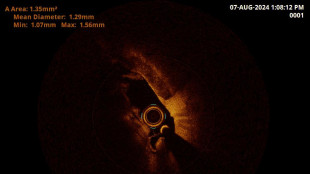

Aritmie, ad Ancona il sistema innovativo di ablazione con Affera

Rapidità, sicurezza, efficacia. Primo ospedale pubblico a usarla